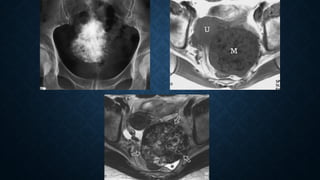

Papillary serous cystadenocarcinoma.

Multilocular mass (solid arrows) around the uterus (U)

Irregular solid components (open arrows)

Intracystic papillary projections (arrowheads).

Papillary serous cystadenocarcinoma. Multilocularmass (solid arrows) around the uterus (U) Irregular solid components (open arrows) Intracystic papillary projections (arrowheads).